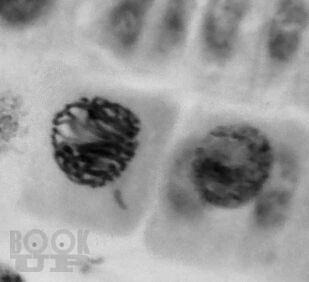

В предлагаемом учебном пособии представлены описания паразитов (простейших, гельминтов и членистоногих), которые являются возбудителями наиболее распространенных заболеваний человека. Материал, представленный в пособии, рассчитан на изучение медицинской паразитологии в течение одного семестра.

Все разделы пособия хорошо иллюстрированы схемами, таблицами, рисунками и фотографиями изучаемых паразитов. В конце каждой главы приведены вопросы для контроля полученных знаний, а также ситуационные задачи и тестовые задания для самоконтроля.